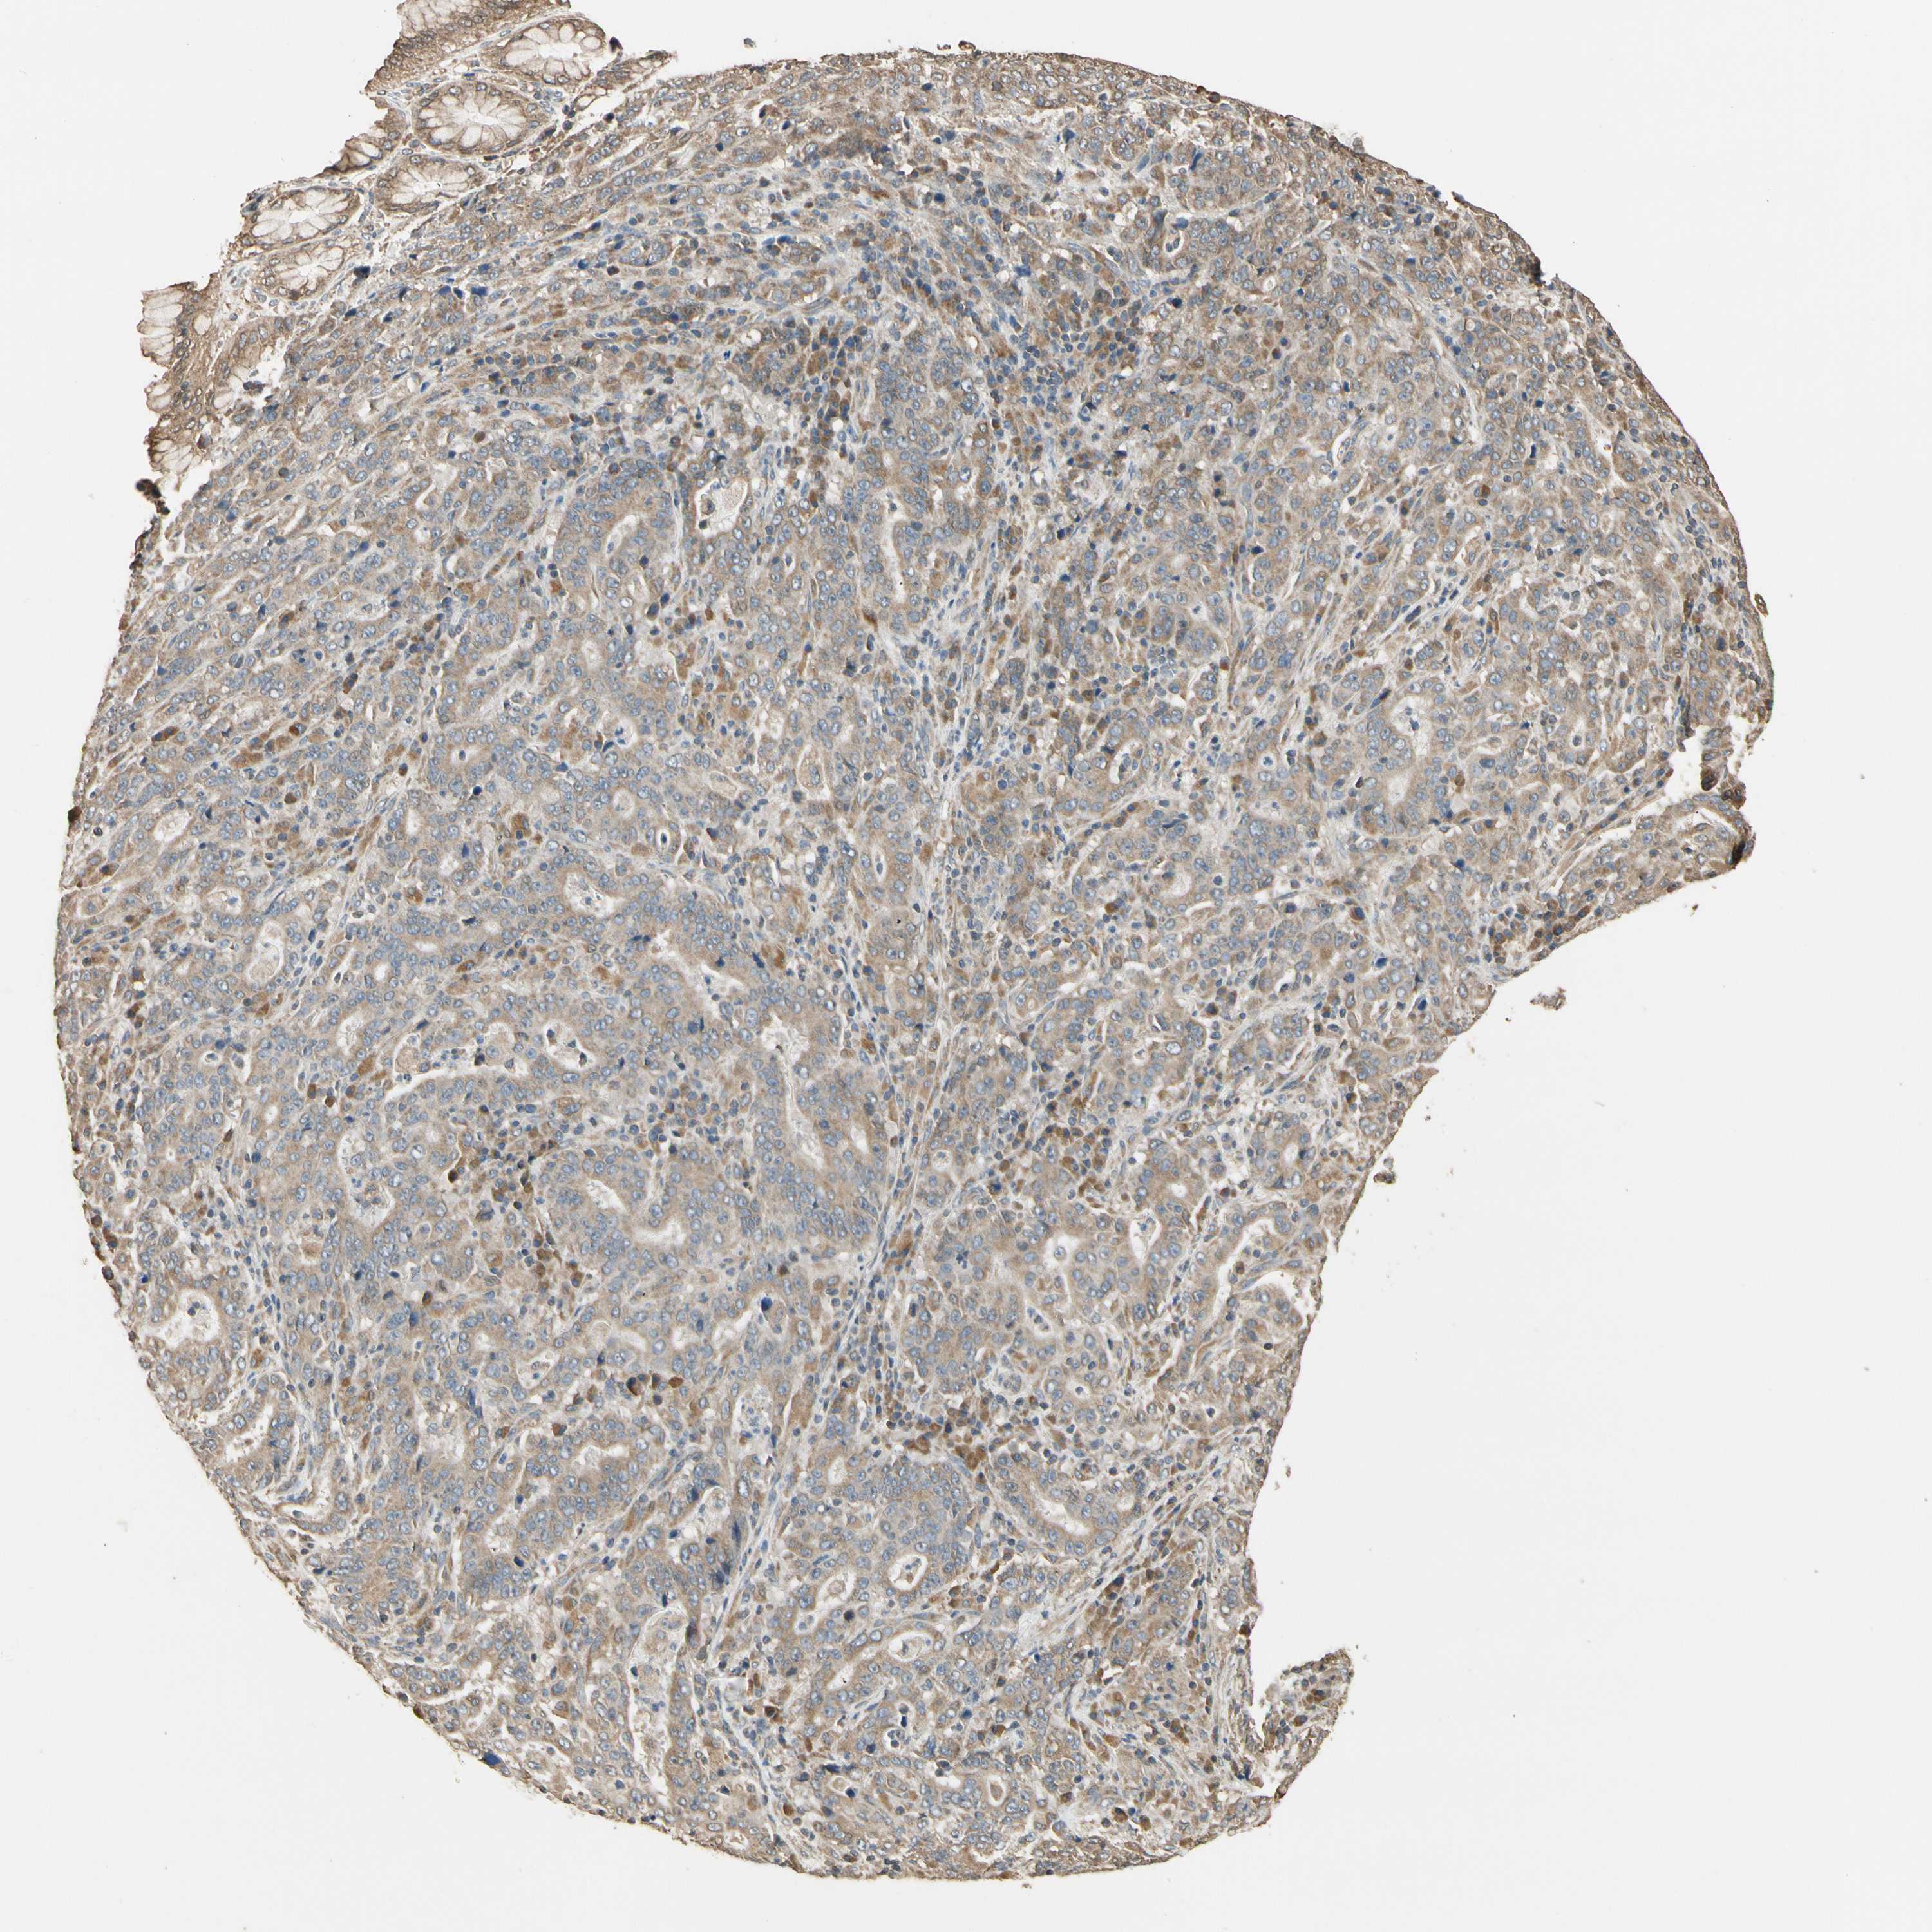

STOMACH CANCER - Protein expressioni

A mouse-over function shows sample information and annotation data. Click on an image to view it in a full screen mode. Samples can be filtered based on level of antibody staining by selecting one or several of the following categories: high, medium, low and not detected. The assay and annotation is described here.

Note that samples used for immunohistochemistry by the Human Protein Atlas do not correspond to samples in the TCGA dataset.

Antibody stainingi

Antibody staining in the annotated cell types in the current human tissue is reported as not detected, low, medium, or high, based on conventional immunohistochemistry profiling in selected tissues. This score is based on the combination of the staining intensity and fraction of stained cells.

Each image is clickable and will lead to virtual microscopy that enables deeper exploration of all samples and also displays staining intensity scores, fraction scores and subcellular localization as well as patient and tissue information for each sample.

Antibody HPA003019

Staining

High

Medium

Low

Not detected

Intensity

Strong

Moderate

Weak

Negative

Quantity

>75%

75%-25%

<25%

None

Location

Nuclear

Cytoplasmic/membranous

Cytoplasmic/membranous,nuclear

Adenocarcinoma, NOS

Adenocarcinoma, High grade